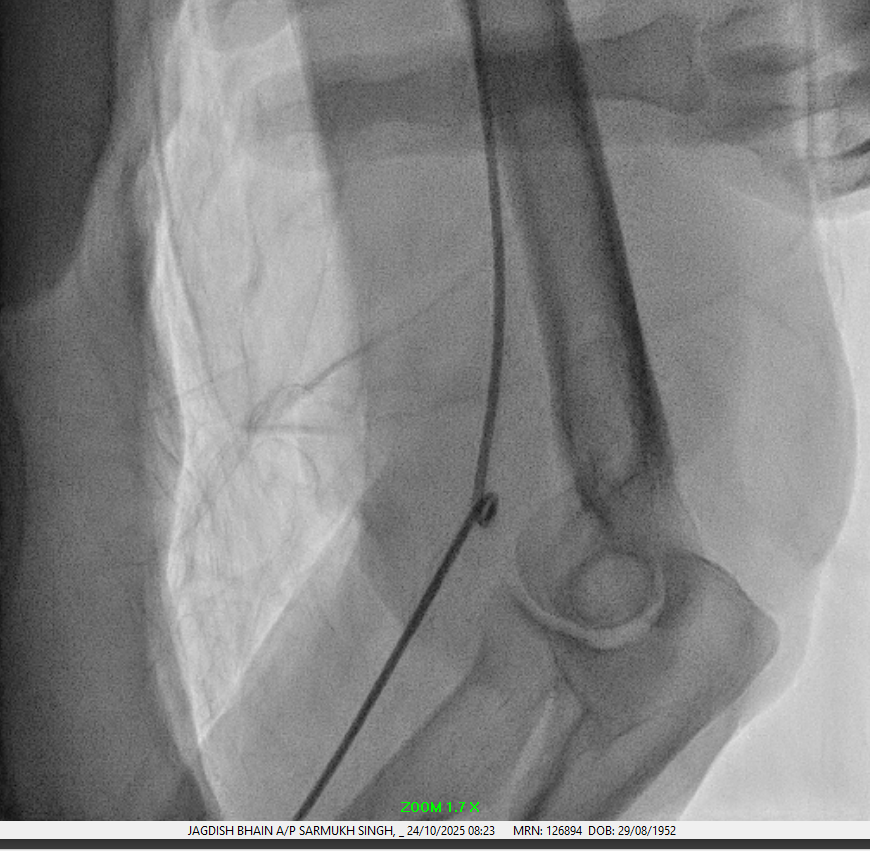

Right femoral puncture and Snare Amplatz Goose Neck 20mm advanced to distal tip of catheter.

Distal tip of catheter was snared and manage to unkink catheter.

Optitorque 5FR catheter successfully removed from left radial sheath.